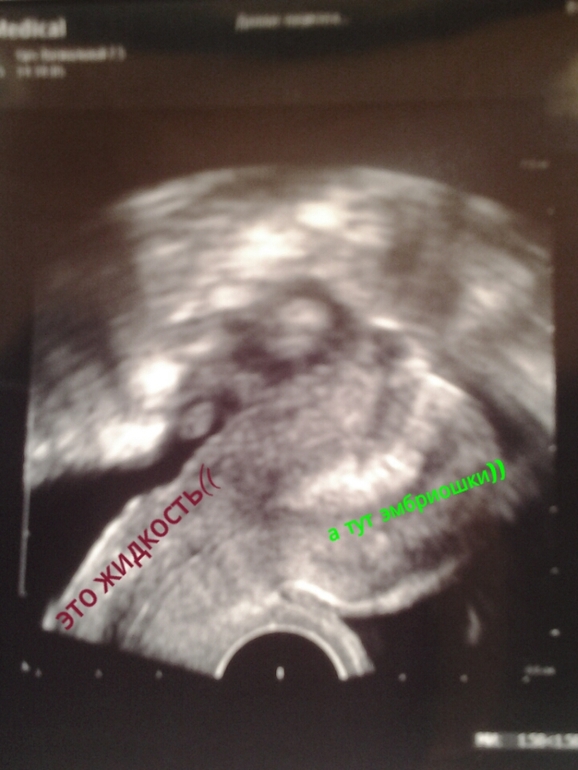

Протоколы ЭКО (Все о них, все об этом периоде+Гиперстимуляция)Хочу вам показать сколько у меня по узи жидкости,доктор сказал не критично по мне так много... прошу под кат под надписью жидкость чернотв это она и есть((( такая страшная,зато вон там где все светиться там эмбриоши и они хорошие))